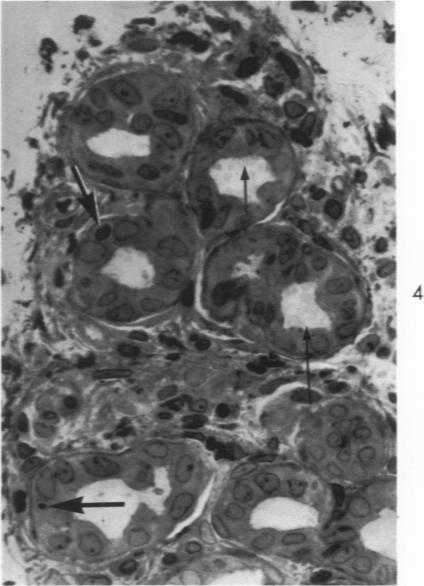

Early changes in the exocrine pancreas of the dog and rat after ligation of the pancreatic duct. A light and electron microscopic study.

Am J Pathol. 1971 Jun;63(3):521-46.